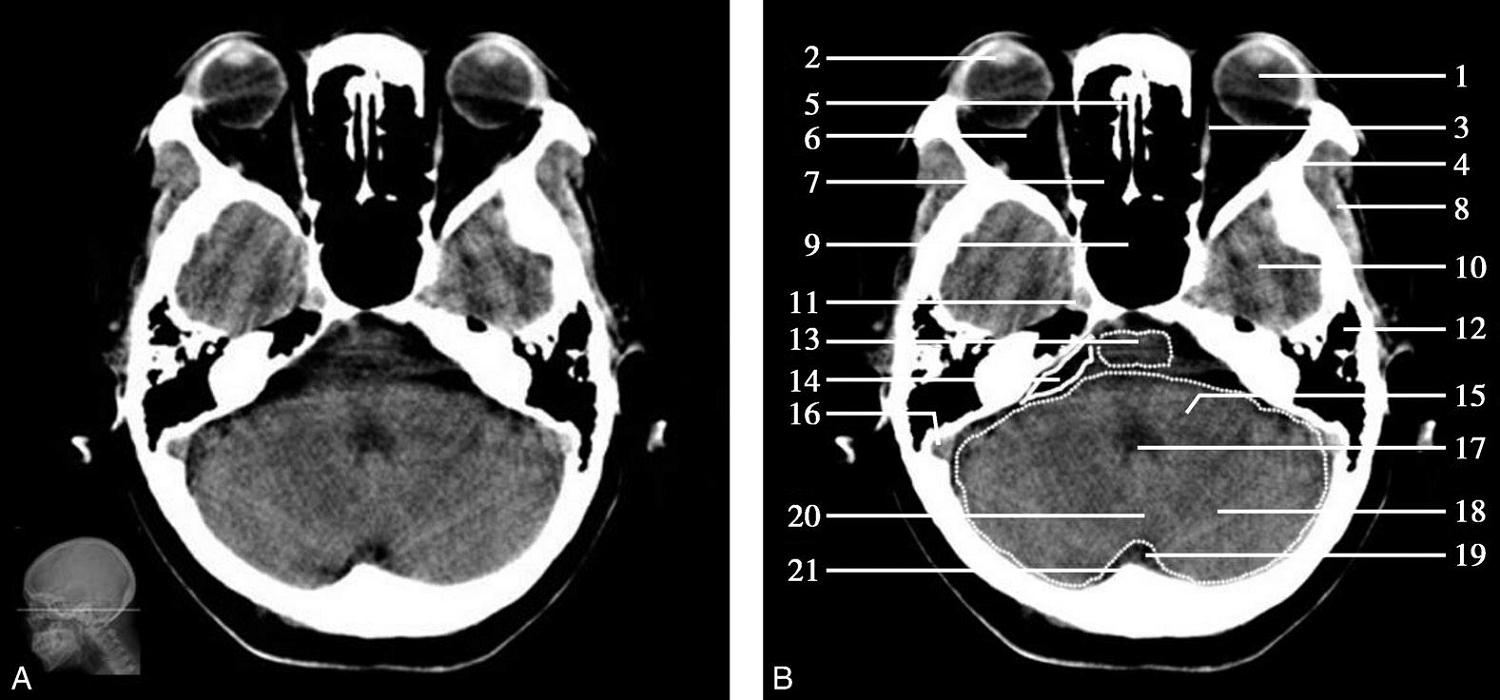

重要结构:卵圆孔、棘孔、破裂孔、斜坡、颞骨岩部、颈静脉孔(图1-2-1、图1-2-2)。

图1-2-1 颅底层面

A.横断面;B.横断面标注

1.晶状体;2.筛窦;3.颞肌;4.中颅窝底;5.外耳道;6.延髓;7.乙状窦;8.小脑半球;9.眼球;10.眼眶;11.上颌窦;12.蝶窦;13.乳突;14.耳郭;15.小脑蚓部;16.枕内隆凸

图1-2-2 颅底层面(骨窗)

1.鼻骨;2.筛窦纸板;3.颧骨眶突;4.翼腭窝;5.蝶骨大翼;6.卵圆孔;7.破裂孔;8.颞骨颧突;9.棘孔;10.斜坡;11.颞骨岩部;12.乳突;13.颈静脉孔;14.枕乳突缝;15.枕骨;16.枕内隆凸

层面前部呈开口向前的“V”字形,正中为鼻中隔,向两侧依次为筛窦和眼眶,眼眶内前部为眼球,后部为眶脂体。翼腭窝位于眼眶后部,窝内含有脂肪并有上颌神经通过。层面中部为蝶骨体,蝶骨体中部可见含气蝶窦,蝶窦后方为枕骨基底部,两者呈前后关系,其上面构成斜坡。蝶窦两侧为蝶骨大翼,其后外侧缘处由前向后可见卵圆孔和棘孔,分别有下颌神经和脑膜中动脉通过。斜坡外侧、岩骨尖前方为破裂孔。蝶骨大翼与眶外侧壁的颧骨借颧弓相连,颧弓和蝶骨大翼之间有咬肌及颞肌。层面中部外侧为外耳道。颞骨岩部呈“八”字形,相互之间借破裂孔软骨、蝶岩软骨结合和岩枕软骨结合连接。岩部后外侧的乳突部内可见乳突小房,乳突部与枕骨相接。岩骨后部可见颈静脉孔,内有颈内静脉、舌咽神经、迷走神经和副神经通过。层面后部为颅后窝,其内可见延髓,延髓前方为延髓前池,内有椎动脉,后外侧为小脑半球下部,后方为第四脑室、小脑扁桃体及小脑蚓部。

破裂孔、卵圆孔、棘孔及斜坡等均为重要的解剖结构,临床常见疾病如鼻咽癌常侵犯上述结构(图1-2-3)。颈静脉孔区较常见的肿瘤为颈静脉球瘤,常伴有颈静脉孔及其邻近骨质的破坏(图1-2-4)。